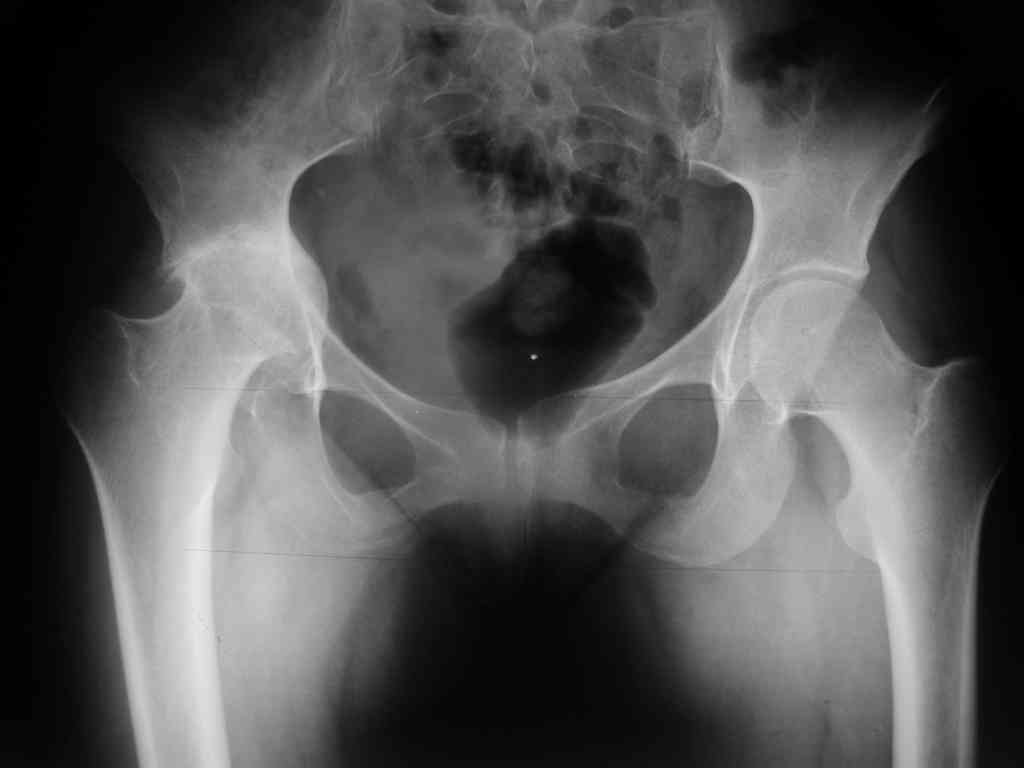

The bridging plate is a weak constuct for angular stresses and hence the deformity. The best option would be a revision THR with an open mind. After exposure one should see the integrity of the cup which is not clearly visible here. The stem is in Valgus and hence the fracture. IT needs to be revised to a long stem like the Wagner system with its 8 fins or a Proximal fit modular stem from J& J. ( both uncemented) Once again plating is not a good option against bending stresses in the femur.

This depends on the stem fixation. If the stem is fixed then it's a Vancouver type B1 fracture and should be fixed with a plate well past the Fx and at least 2-3 shaft diameters above the Fx site proximally (fixed with cerclage wires proximally).

If the stem is loose (Vancouver B2), then it needs to be revised to a longer prosthesis.

Vancouver classification is useful. If implant is stable & well osseointegrated, This # which falls in B1 category with no loss of bone stock,plate osteosynthesis rather than the formidable revision is preferred. I would like to quote following article which is worth going thro'.

according to the Vancouver classification thi looks like a B1 type so ORIF is indicated.

This kind of plate is "forbidden" in literature because has bad results with failure at 1 or 2 months.

The correct ORIF is with a LCP system with a good fixation either proximally or distally (longer than this one).